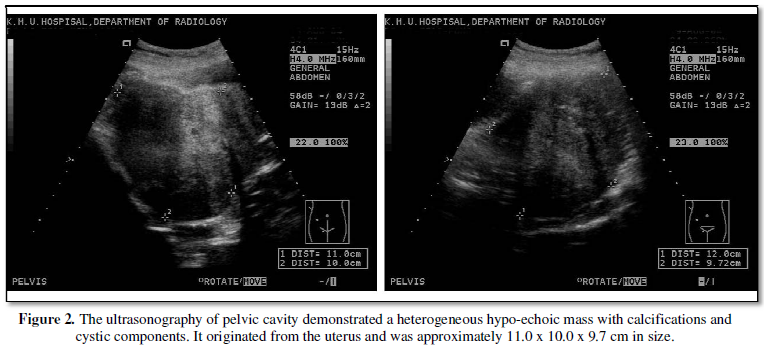

Then ultrasonography was arranged to evaluate the pelvic mass, which

demonstrated a heterogeneous hypo-echoic mass with calcifications and cystic

components. It originated from the uterus and was approximately 11.0 x 10.0 x

9.7 cm in size (Figure 2). The